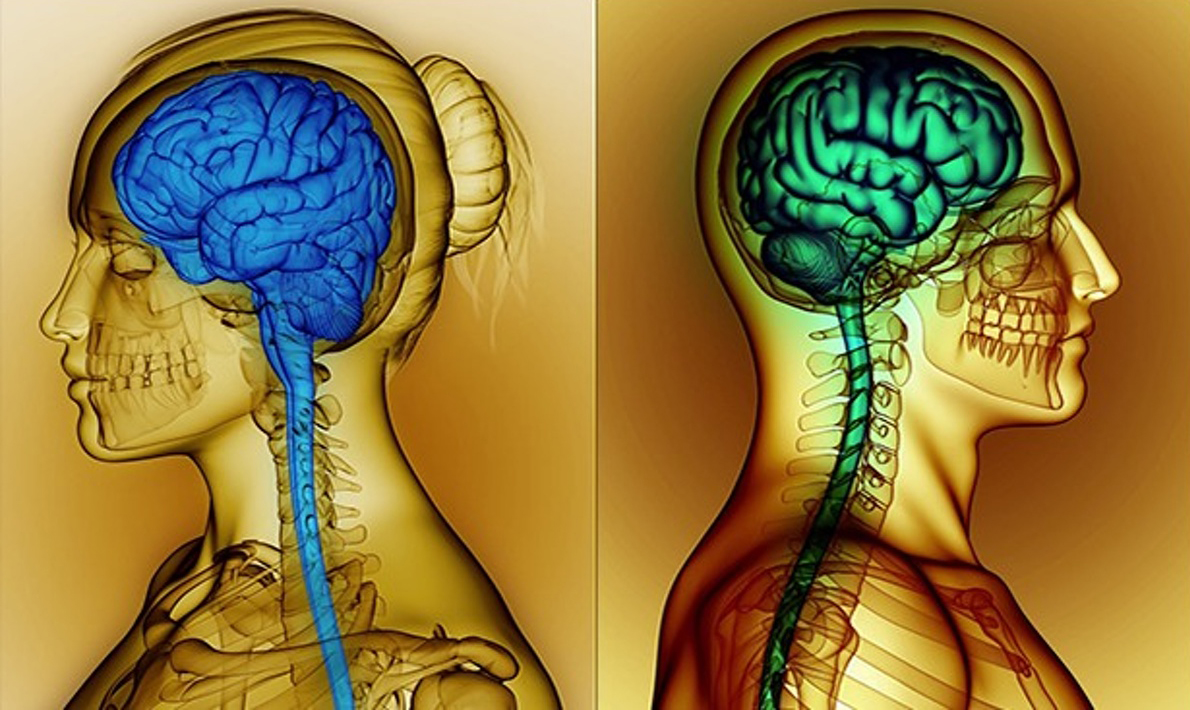

Изучите анатомию женской фигуры, чтобы создать максимально реалистичную имитацию.